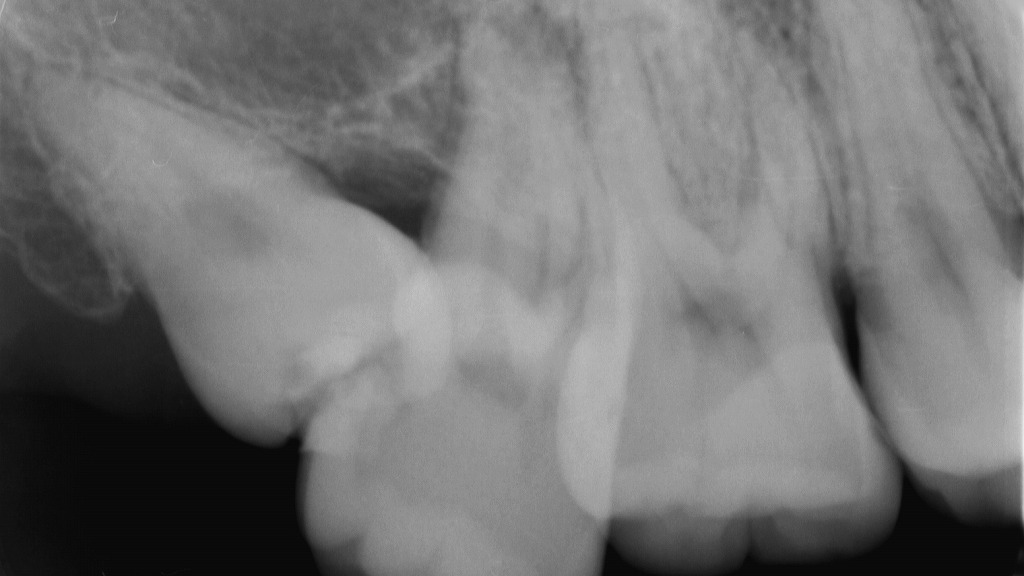

📸 デンタル(口内法)レントゲン

- 特徴:1〜3本の歯をピンポイントで撮影

- 用途:虫歯の進行具合、歯の根や骨の状態を詳細に確認できる

- メリット:被ばく量が少なく、細かい診断に最適

🦷 親知らずや根管治療の診断

- 親知らずが骨の中でどの方向に生えているかを確認

- 神経の炎症や根の先の膿など、見えないトラブルを正確に診断できる

👉 レントゲンなしで治療すると、神経や血管を傷つける危険性もあります。